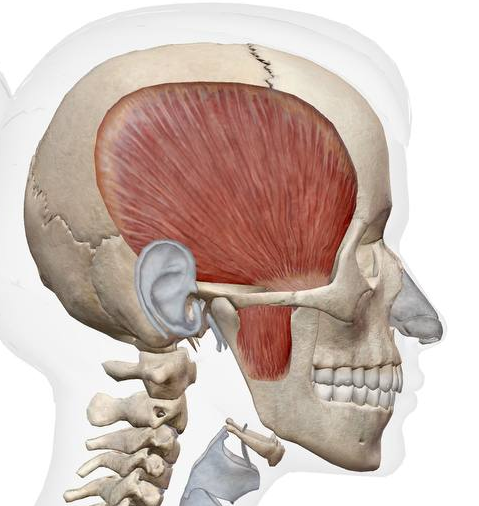

하관혈을 초음파로 살펴보면

측두근(temporalis), 교근(masseter),

내측 / 외측 익돌근(lateral pterygoid)과

턱관절(TMJ) 상태를 볼 수 있고요.